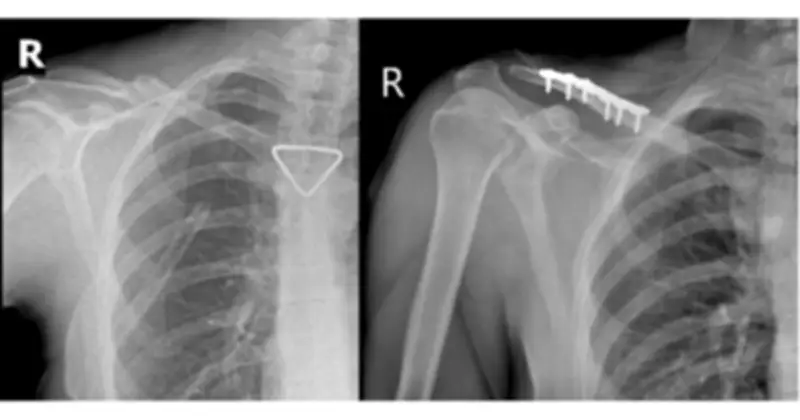

Qua hội chẩn liên chuyên khoa và đánh giá của bác sĩ gây mê hồi sức, bệnh nhân được xác định đủ điều kiện an toàn để thực hiện phẫu thuật kết hợp xương đòn phải bằng nẹp vít. Ca mổ do ê-kíp BSCKII Trần Văn Dương và BS Phạm Ngọc Huy thực hiện, diễn ra thuận lợi với nẹp vít được đặt vững chắc và trục xương phục hồi giải phẫu tốt.